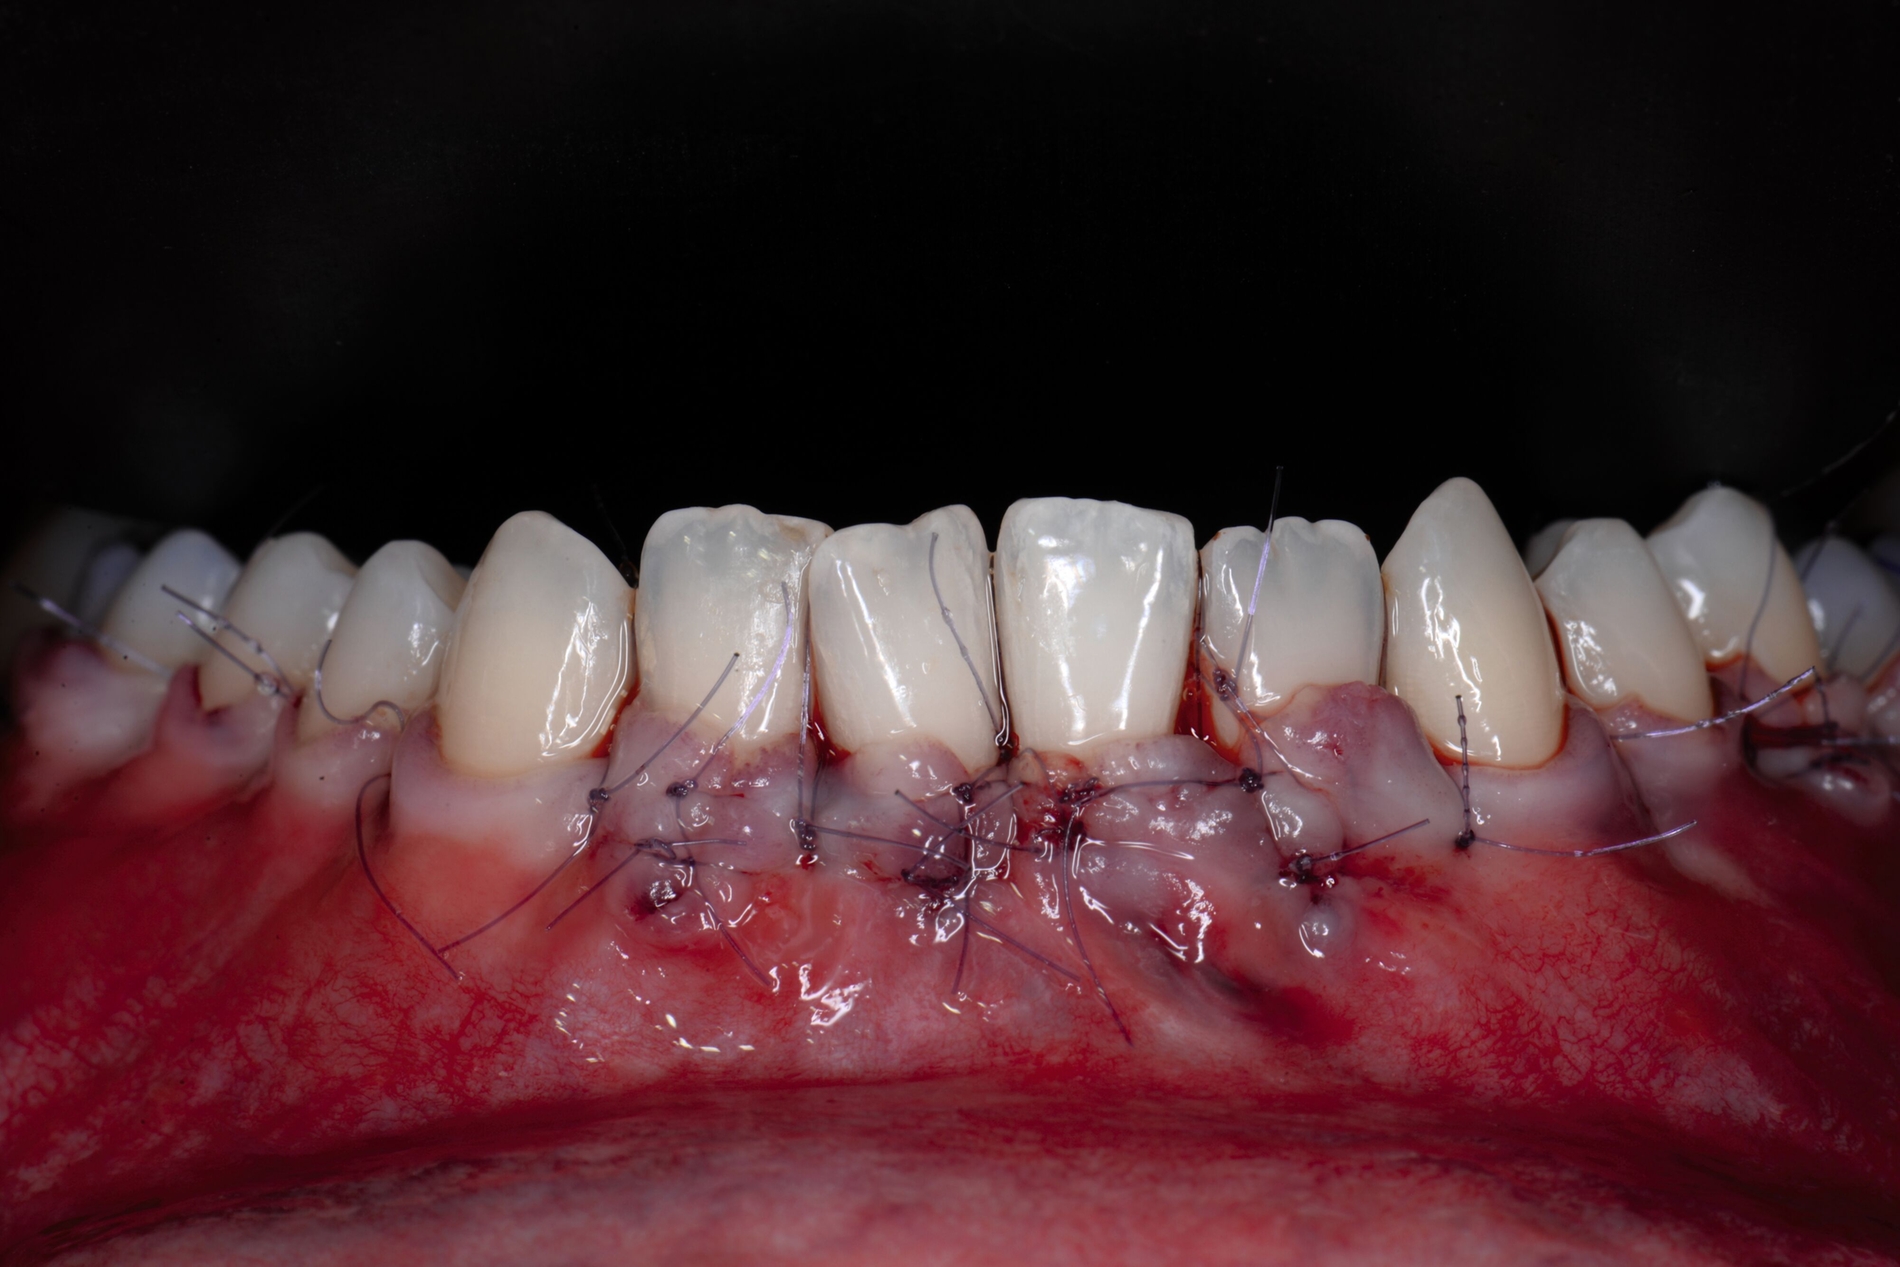

Tunkel et al. versuchten die Vorteile von Zucchellis Koronalem Verschiebelappen und Sculeans Lateral Geschlossenem Tunnel in einer Technik zu vereinen: dem Lateral Geschlossenen Koronalen Verschiebelappen (LCAF) [Tunkel et al., 2024] (Abbildung 3). Bei dieser Methode, mit der vor allem tiefe singuläre parodontale Rezessionen behandelt werden, wird die Koronalverschiebung ohne Entlastungsinzisionen kombiniert mit dem lateralen Verschluss der tiefen parodontalen Rezession.

Das Vorgehen ist hier wie folgt: Zunächst wird im Bereich der tiefen Rezession der Gingivarand geringfügig exzidiert, um ein Zusammenwachsen der geschlossenen Lappenanteile zu ermöglichen. Anschließend wird der Schnitt in horizontaler Richtung durch leicht bogenförmige Schnittführungen auf Höhe der Schmelz-Zement-Grenze erweitert, um mindestens zwei Zähne rechts und links von der Rezession (Abbildung 3b). Im Unterkiefer-Frontzahnbereich, wo die Rezessionen heutzutage am häufigsten vorkommen, sollte der Lappen mindestens von Eckzahn zu Eckzahn gebildet werden, um ein harmonisches Ergebnis nach Abheilung zu erreichen. Auf vertikale Entlastungsinzisionen kann komplett verzichtet werden. Anschließend erfolgt die Lappenpräparation nach dem bereits für koronale Verschiebelappen gängigen Prinzip teilschichtig-vollschichtig-teilschichtig.

Die Papillenbereiche werden mit dem Skalpell scharf vom Periost abgelöst. Dann wird das Periost durchtrennt und bis zur mukogingivalen Grenze ein vollschichtiger Lappen gebildet. Nach Überschreiten dieser wird wieder zweischichtig präpariert. Hierdurch wird eine gute Mobilisation des Lappens erreicht, die eine ausreichende Koronalverschiebung ermöglicht. Entgegen dem in früheren Jahren propagierten komplett teilschichtigen Vorgehen, kann durch dieses Verfahren die Gefahr von Lappenperforationen signifikant gesenkt werden, da diese insbesondere im Bereich der mukogingivalen Grenze auftreten. Nachdem die Lappenareale mesial und distal der Rezession gelöst sind, können diese durch zwei bis drei feine monofile Nähte miteinander verbunden werden (Abbildung 3c). Sobald durch diese Naht ein zusammenhängender koronaler Verschiebelappen entstanden ist, werden die Papillenbereiche koronal des gebildeten Lappens entepithelialisiert. Nach Entnahme eines Bindegewebstransplantats oder entepithelialisierten freien Schleimhauttransplantats wird die Wurzeloberfläche mit EDTA-Gel konditioniert und anschließend werden Schmelz-Matrix-Proteine aufgetragen (Abbildung 3d). Diese bewirken die Bildung eines new attachment und fördern zudem die Wundheilung, was gerade bei den delikaten lateralen Verschiebelappen von Vorteil sein sollte [McGuire und Cochran, 2003; Almqvist et al., 2011; Thoma et al., 2011; McGuire et al., 2016]. Anschließend wird das Transplantat durch Nähte ausgehend vom oralen Papillenbereich fixiert (Abbildung 3e). Zuletzt wird der Lappen mit sogenannten doppelten Umschlingungsnähten im Bereich der Papille durch Zug nach koronal und oral fixiert, was eine perfekte Positionierung ermöglicht [Zuhr et al., 2009] (Abbildung 3f). Hierbei muss darauf geachtet werden, dass der Lappen die Schmelz-Zement-Grenze um mindestens 2 mm überdeckt, um eine hundertprozentige Wurzeldeckung erwartbar zu machen [Pini Prato et al., 2005].

Der Lateral Geschlossene Koronal Verschobene Lappen ermöglicht eine annähernd narbenfreie Deckung singulärer parodontaler Rezessionen durch Verzicht auf vertikale Entlastungsinzisionen (Abbildung 3g). Das Lösen der Papillen im Rahmen der Verschiebung ermöglicht eine deutliche Anhebung des Lappens und somit durch großzügige Überdeckung das Erreichen vollständiger Wurzeldeckungen. Durch den lateralen Verschluss im Rahmen der tiefen, über die mukogingivale Grenze hinausgehenden Rezession kann keratinisierte Gingiva im Bereich dieser hergestellt und eine übermäßige Mobilisation und damit Einschränkung des Vestibulums verhindert werden.